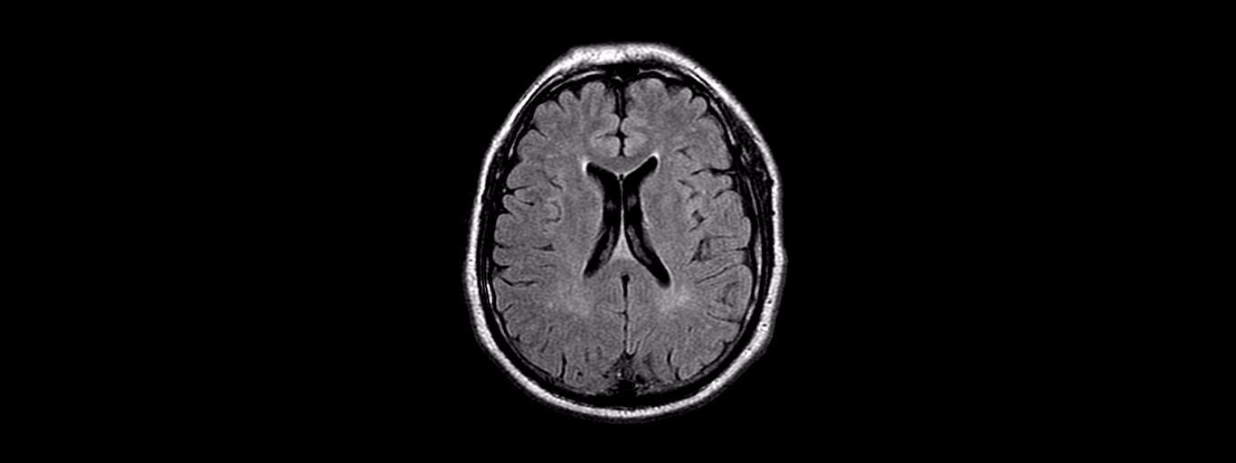

Resonancia Magnética

Es un análisis seguro e indoloro en el cual se utiliza un campo magnético y ondas de radio para obtener imágenes detalladas de los órganos y las estructuras del cuerpo.

En la resonancia magnética no se utiliza radiación y ésta es una de las diferencias que tiene con la tomografía.

A continuación puedes consultar información general acerca de algunos de los estudios de Resonancia Magnética que tenemos disponibles, solamente da un clic en la imagen deseada: